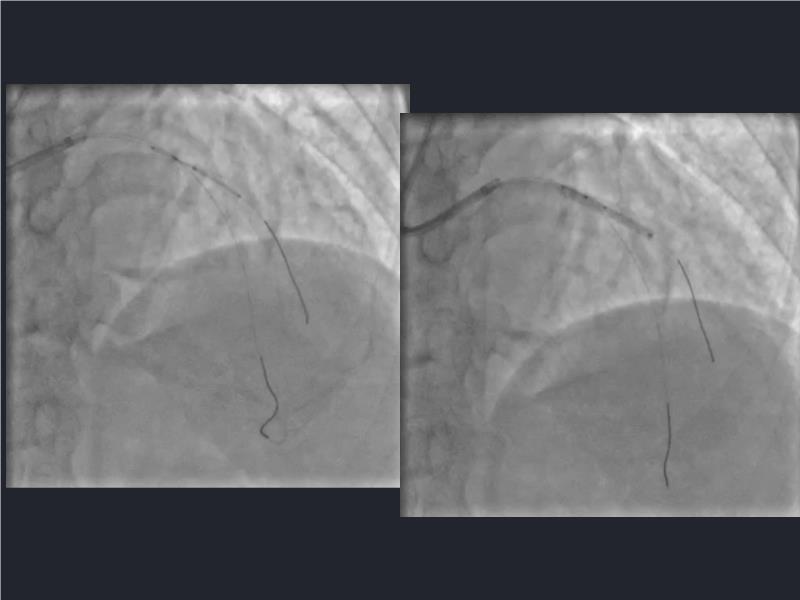

This session is a valuable resource for grasping innovative strategies in handling bifurcation and extended diffuse lesions through dedicated stenting solutions. Explore insights into the advanced Myval next-generation THV technology, unveiling its distinctive features, procedural advantages, and clinical outcomes across a diverse patient pool. Gain understanding into the CorAlign technique, ensuring accurate commissural and coronary alignment while maintaining coronary access. Additionally, delve into the techniques for precise sizing, positioning, and deploying of Myval THV.

- To understand novel tools and techniques for effective management of bifurcation lesions and long diffused lesions using dedicated stenting solutions